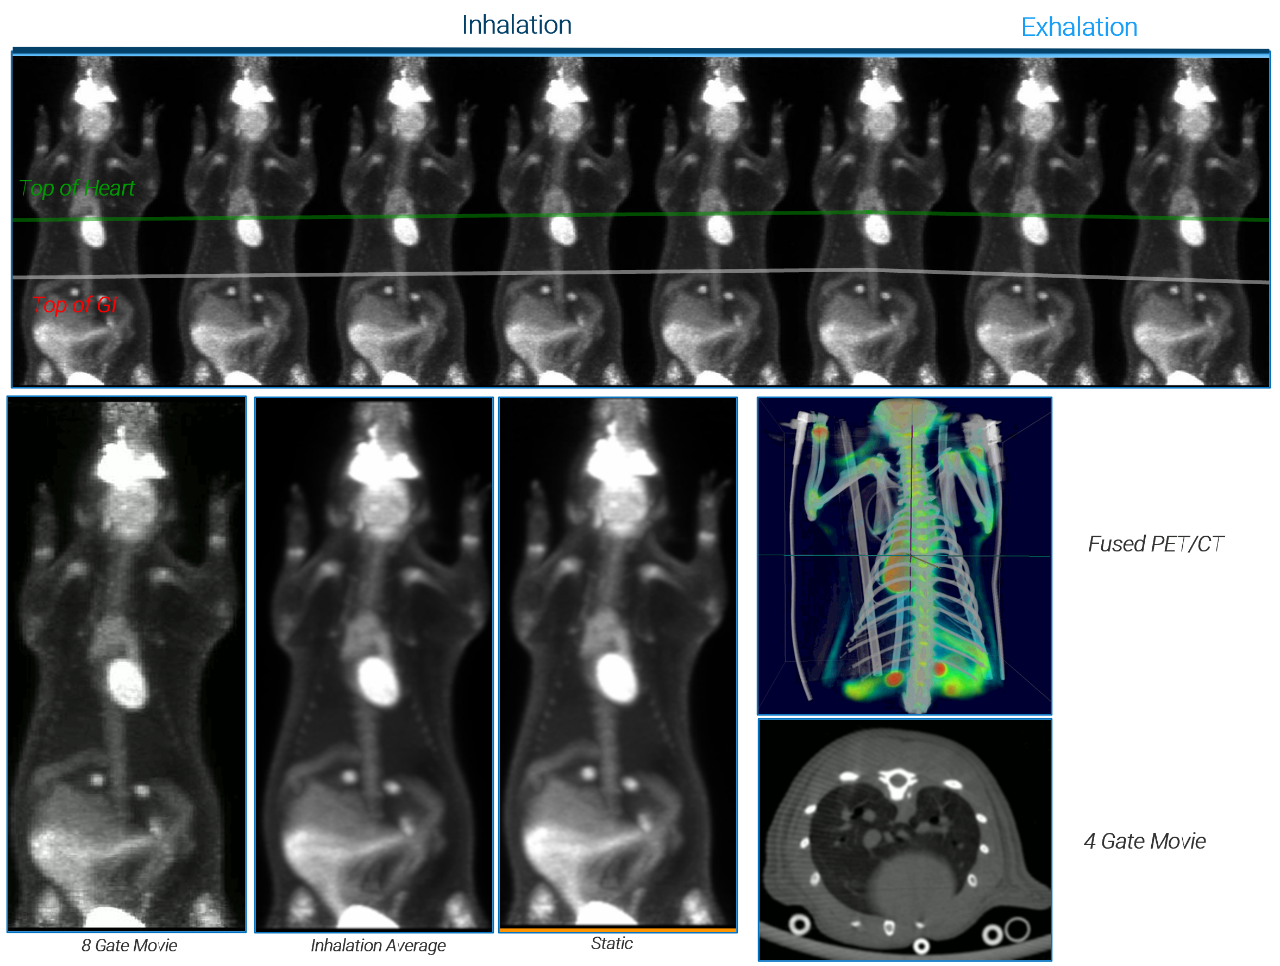

The PET/CT Si78 is a molecular imaging system for sequential Positron Emission Tomography (PET) and X-Ray Microtomography (uCT). The fully shielded scanner, the animal welfare solutions and the experimental workflows are designed to support high throughput translational preclinical research in all field s of nuclear molecular imaging research.

PET Features

• Up to 0.7 mm spatial resolution

• Up to 12 % sensitivity

• 150 x 80 mm FOV

• True DOI, no loss of resolution across FOV

• Ultrafast GPU reconstruction (MLEM, OSEM and MAP)

CT Features

• Gated cardiac imaging